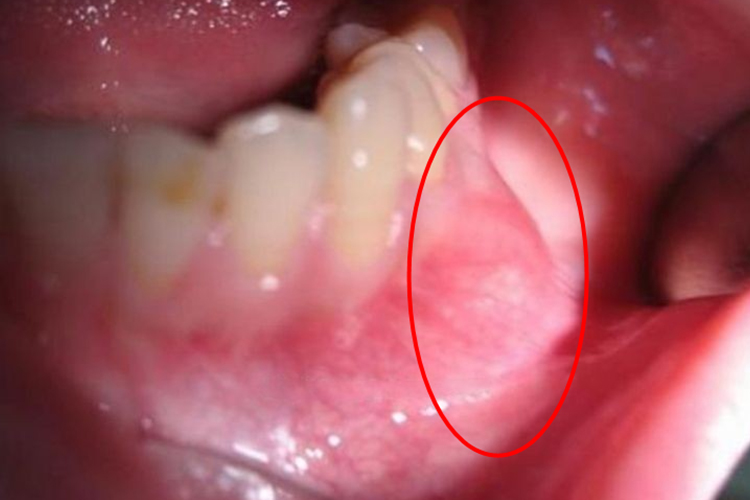

下颌骨骨化纤维瘤主要表现为颌骨呈膨大状态,肿瘤质硬,界限不清,可造成面部畸形、咬合紊乱,有时可继发感染,伴发骨髓炎。影像检查表现为类圆形肿块或不规则形肿块,多可见完整包膜。